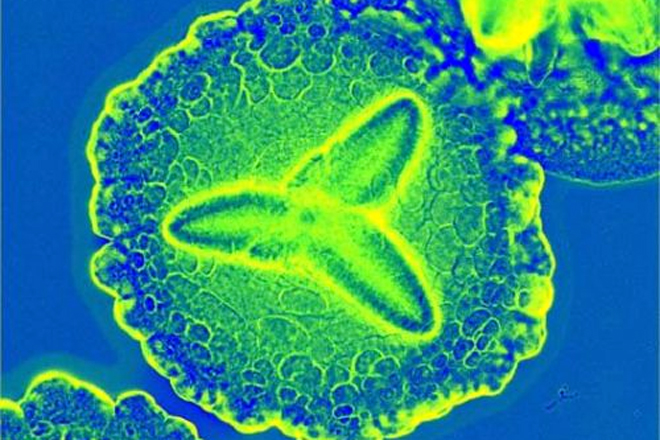

Бактерия, которая является близкой "родственницей" возбудителя гангрены, столбняка и пищевых отравлений может помочь ученым вылечить рак. Предварительные тесты на мышах показали многообещающую эффективность данного метода. Разработчики нового метода уверены, что таким способом им удастся лечить большинство видов рака. Стратегия излечения при использовании данного метода базируется на уникальных свойствах как опухолевой ткани, так и самой бактерии. С одной стороны, опухоль всегда испытывает недостаток в кислороде из-за малого диаметра питающих ее сосудов. С другой стороны, клостридии лучше всего чувствуют себя именно в бескислородной среде. Метод зародился как продолжение других разработок: ранее для переноса препаратов от рака использовались частицы - наносомы. Однако практика показала, что они слишком крупны, чтобы проходить по узким сосудам, питающим опухоль, и могут задерживать препарат внутри себя. Для ускорения процесса высвобождения было предложено использовать бактериальный переносчик. Бактерия, попадая в очаг, высвобождает фермент, который назван липосомазой, и разрушает стенки наполненных лекарством липосом. Большая часть лабораторных мышей, больных раком кишечника, полностью излечились от заболевания после единственной дозы такой терапии. Кроме того, такое лечение очень хорошо переносилось мышами и не вызывало побочных эффектов. Новый метод лечения будет исследован и опробован на людях. Ученые считают, что это даст потрясающие результаты.